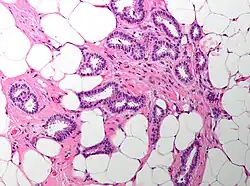

| Cribriform carcinoma of the breast showing a cribriform area | |

Invasive cribriform carcinoma of the breast (ICCB), also termed invasive cribriform carcinoma, is a rare type of breast cancer that accounts for 0.3% to 0.6% of all carcinomas (i.e. cancers that develop from epithelial cells) in the breast.[1] It originates in a lactiferous duct as opposed to the lobules that form the alveoli in the breasts' mammary glands (lobules make the milk which the ducts channel to the breast's nipple). ICCB was first described by Dixon and colleagues in 1983 as a tumor that on microscopic histopathological inspection had a cribriform pattern,[2] i.e. a tissue pattern consisting of numerous "Swiss cheese"-like open spaces and/or sieve-like small holes (see adjacent Figure).[3] The latest edition (2019) of the World Health Organization (2019) termed these lesions invasive cribriform carcinomas indicating that by definition they must have a component that invades out of their ducts of origin into adjacent tissues. In situ ductal cancers (i.e. cancers localized entirely within their tissues of origin) that have a cribriform histopathology are regarded as belonging to the group of ductal carcinoma in situ tumors.[4]

The microscopic histopathology of ICCB tumors stained with hematoxylin and eosin shows cribriform areas covering more than 50% of the tumor with the remaining tumor areas showing tubular and/or other histopathological patterns. The cribriform areas consist of small-sized cells with amphophilic (i.e. taking up both the hematoxylin and eosin stains) cytoplasm, indistinct cell boundaries, and small-to-medium sized nuclei that are surrounded by a sharp nuclear membrane and contain finely stippled chromatin (i.e. DNA coated with protein).[17] Numerous open spaces and/or sieve-like small holes lie between these cells (see above photomicrograph) to give the lesions a Swiss cheese-like appearance. The spaces and holes may contain microcalcifications and/or mucins (i.e. high molecular weight, sugar-linked proteins normally produced and secreted by the mammary gland and found in milk).[3] The cells around these spaces and holes sometimes have "apical snouts", i.e. small protrusions on the side of the cells that faces the spaces and holes.[11] Tubular areas (see adjacent photomicrograph of a tubular carcinoma) consist of well-formed tubules lined with mostly normal appearing tubular cells.[17][20] The other histopathological patterns that may occur in these tumor types include the pattern associated with invasive carcinoma of no special type[4] or in uncommon cases the pattern associated with mucinous carcinoma of the breast.[17] The invasive component of these tumors almost always has the cribriform histopathology pattern.[14] All of the tumor cells in ICCB are typically slow-growing as evidenced by their low mitotic index (i.e. the ratio of the number of dividing cells to the total number of tumor cells) or low levels of cellular Ki-67 protein (an index of cell proliferation).[14]